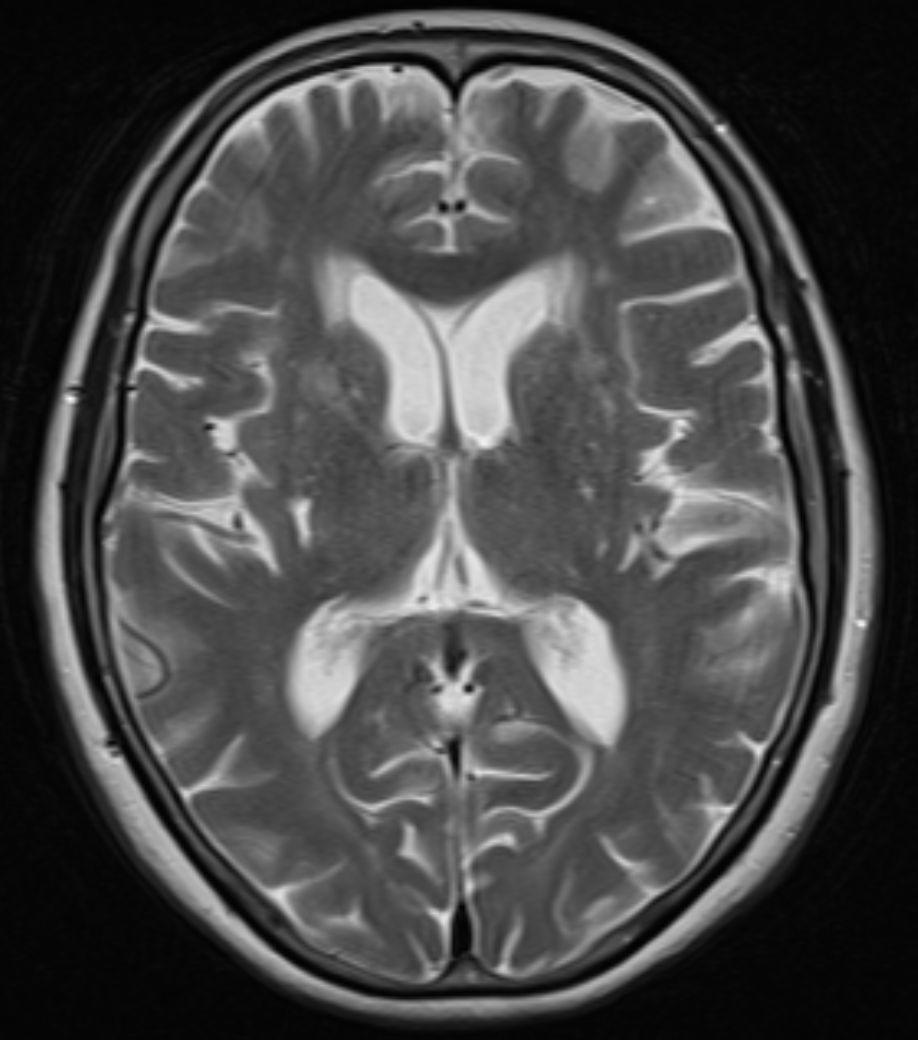

無症候性脳梗塞は赤丸

大脳白質病変は黄丸

無症候性脳梗塞も大脳白質病変も脳の虚血性変化ですが、

大脳白質病変と違うところは、加齢現象ではなく、これは「脳梗塞」であり、小さくても血管が詰まったということです。